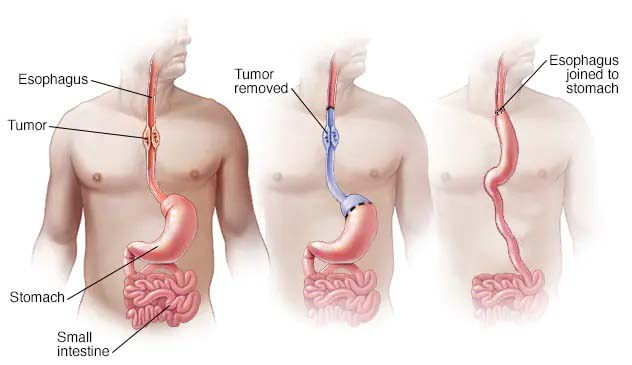

Esophagectomy Purpose Preparation Procedure Aftercare Recovery Risks

Esophagectomy Esophageal Surgery In Mumbai Dr Shitesh Malewadkar